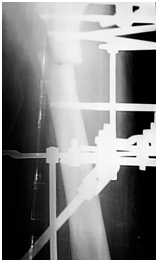

The fracture united at 22 weeks, which is within the range documented in literature.4,5 A major contributing factor to the healing is the ICD‘tension-stress’ principle, which coupled with the micro-motion at bone-wire interface stimulates osteogenesis, angiogenesis and desmogenesis.8 An important component to the system is the specially designed Russian 1.8millimeter bio-compatible bayonet olive-wires we used. The sharp ‘cutting-tips’ of these wires permit a faster, and hence a more efficient bone penetration. This in-turn, optimizes operative time by preventing equipment failure, and most importantly minimizes periosteum and tissue damage- aiding to faster healing and union (Figure 7).